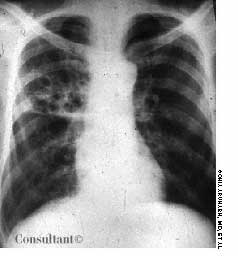

Having been treated for pulmonary tuberculosis (TB) 25 years earlier, a 60-year-old man (a nonsmoker) now complained of a chronic cough. The cough was occasionally accompanied by yellowish sputum but no hemoptysis. Examination revealed persistent coarse crackles in the right posterior hemithorax, and the x-ray study seen here established the diagnosis of cystic bronchiectasis.